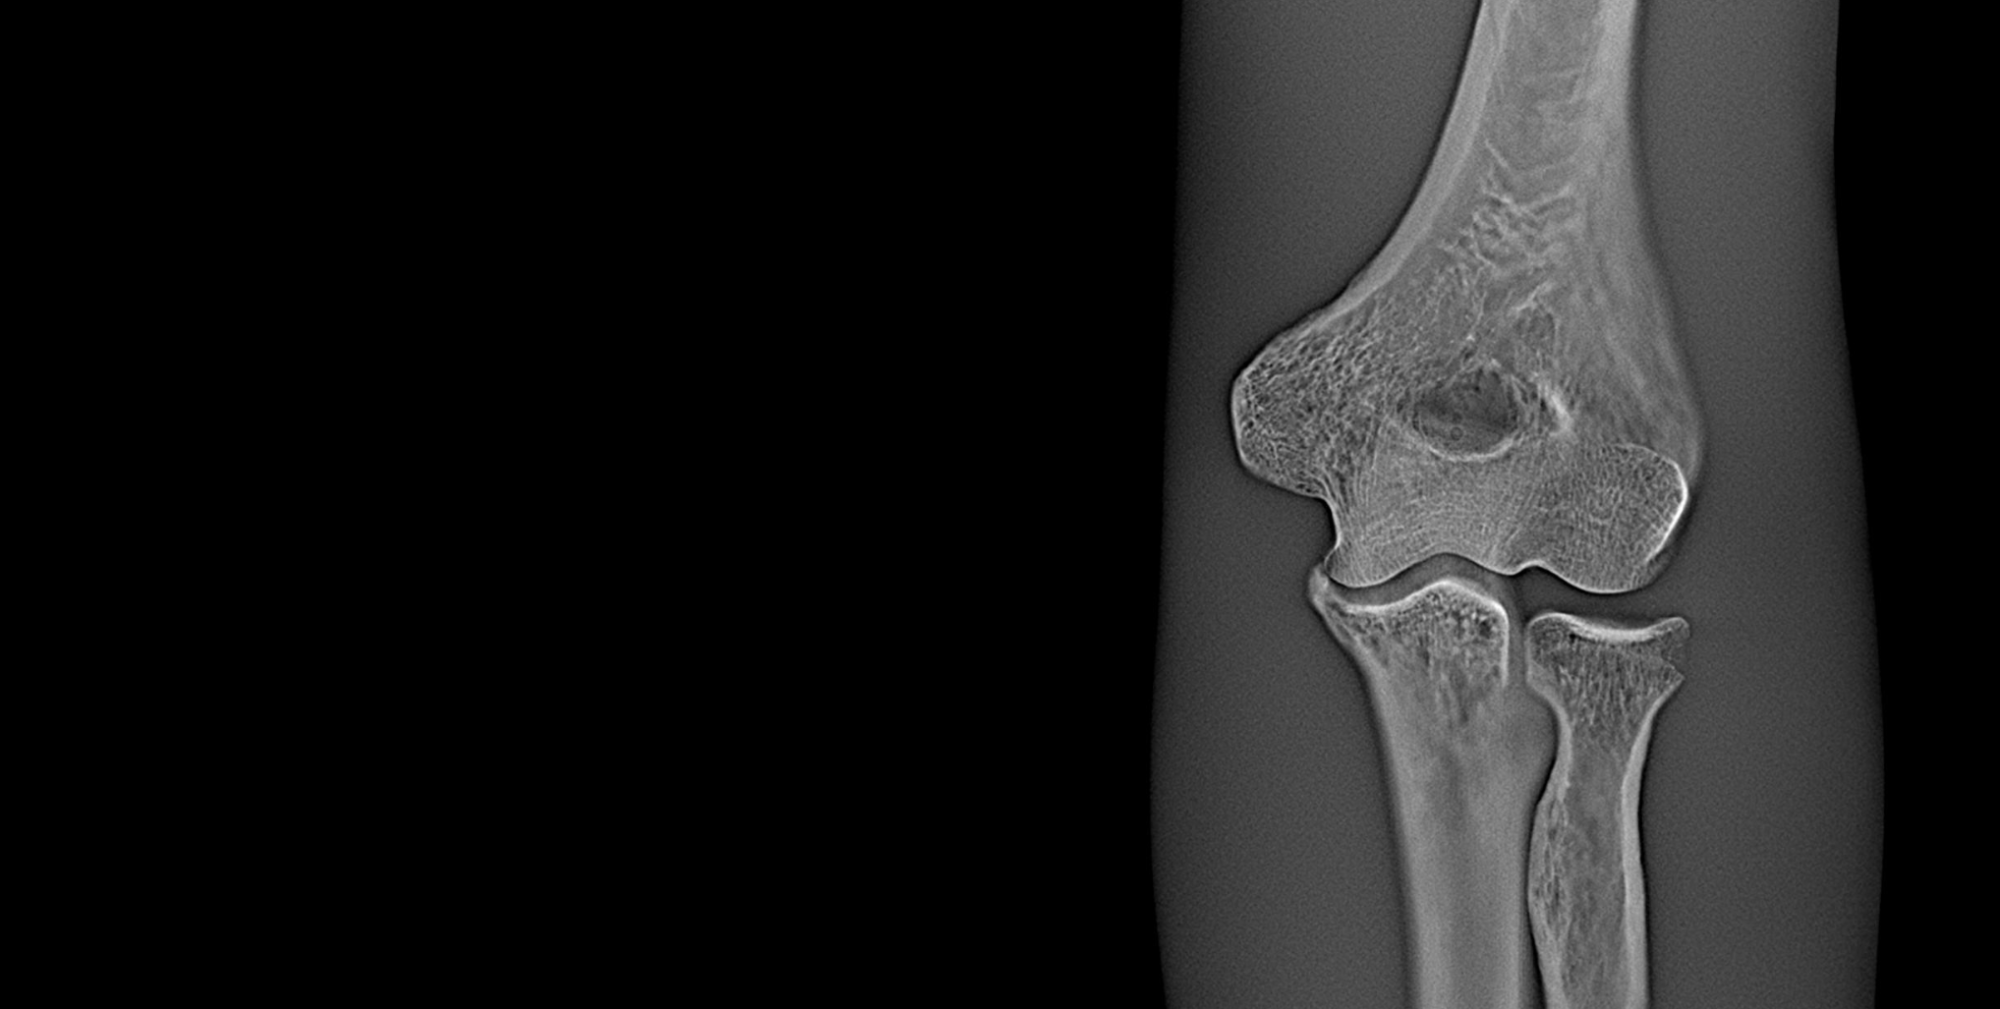

The Adaptix Ortho350 is a cutting-edge, portable Digital Tomosynthesis (DT) system designed to provide high-resolution, low-dose 3D imaging for musculoskeletal diagnostics. This revolutionary system addresses the limitations of traditional 2D X-ray imaging while offering a more accessible, cost-effective alternative to full CT scans.

This advanced hardware innovation enables the rapid acquisition of multiple low-dose X-ray projections from different angles, which are then reconstructed into a highly detailed, depth-resolved 3D image. This allows clinicians to visualise complex bone structures with greater clarity, improving diagnostic accuracy for fractures, joint conditions, and degenerative diseases.